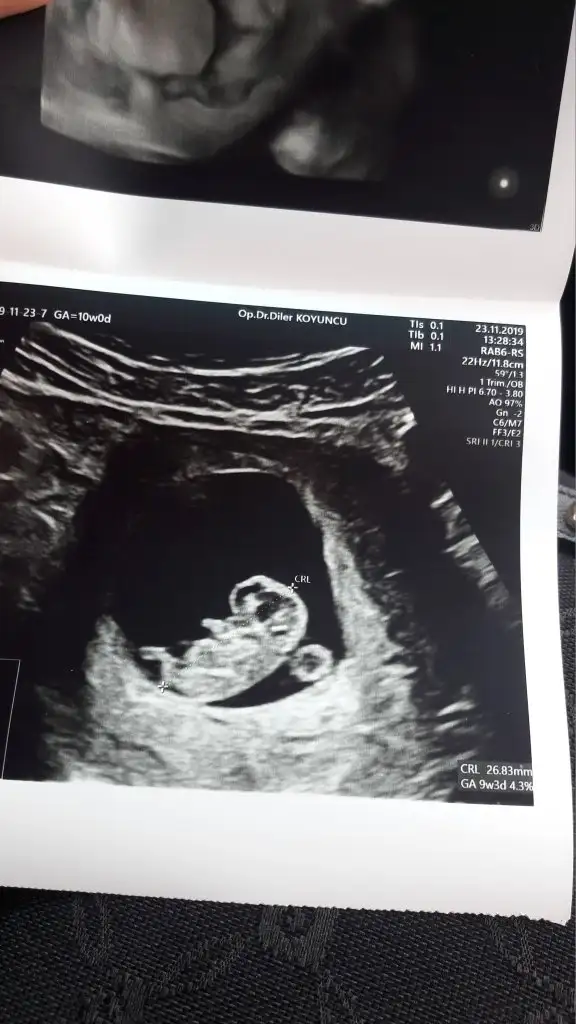

Merhaba kizlar Dr dan geldim devlet hastanesi olunca 10 sn ultrasonda anca baktı sormadım bende cinsiyeti falan ama kendi drma gidince sorucam kan falan verdim yorum yapabilecek varsa resmi atıyorum , nuba falan 😄12 hafta 6 günlük çıktı el salladı bana 😁Eki Görüntüle 2566468 Eki Görüntüle 2566469

Canım nub fotografı almamış tahmin yapmak çok zor ama skull teorisine göre erkek. Skull teorisi kemik yapısına göre cinsiyet tahmini dedikleri şey. Genital çıkıntıya değil kafa tası, çene kemiğine vs bakılıyor. Gerçi skull nuba göre daha fazla yanılıyor. Yine de çok iyi bir erkek skull örneği minnoş kafası :)

Dorothyy Dorothyy BENMKİDE SKULL A GÖRE ERKEK DİMİ :D

Eveet annesi :) ama seninki daha çok minik.11-12. haftalarda olursa daha net belli oluyor kafa yapısı. Bak sana örnek atayım biraz büyüyünce karşılaştırırsın. Kızların çene ve kafa tası daha yuvarlakken erkeklerin daha kemikli ve sert geçişli oluyor. Bir de kızların alnı düz inerken erkelkerde bir tümsek oluyor. Senin minnoşta da var. Ama nub a göre daha fazla yanılıyor skull.